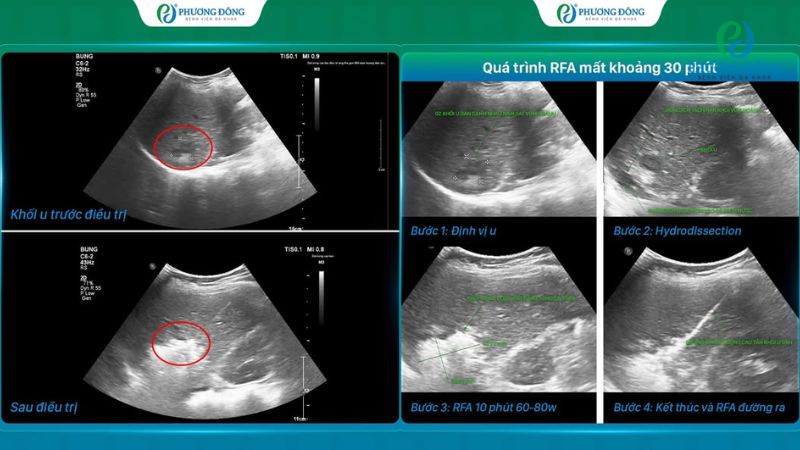

Theo BSCKII.BSNT Ngô Quang Định, ca ung thư gan của nữ bệnh nhân 66 tuổi có độ phức tạp cao do vị trí khối u nằm sát vòm hoành, gần tĩnh mạch chủ dưới và cực trên thận phải. Tĩnh mạch, thận đều là những cấu trúc quan trọng của cơ thể, đặt ra yêu cầu về kỹ thuật can thiệp chính xác cao. Bao gồm việc tiêu diệt triệt để hai khối u ác tính nhưng vẫn đảm bảo tính toàn vẹn cho vùng mô và bộ phận lân cận.

Trước những vấn đề thực tế về bệnh tình và mục tiêu điều trị đề ra, ekip đã áp dụng kỹ thuật bơm tách dịch (hydrodissection) để tạo khoảng cách giữa gan với các cơ quan lân cận trước khi tiến hành RFA. Toàn bộ quá trình thực hiện thủ thuật diễn ra trong khoảng 30 phút, bệnh nhân sau đó hoàn toàn tỉnh táo, gần như không đau và ghi nhận phục hồi nhanh chóng chỉ sau 24 giờ.